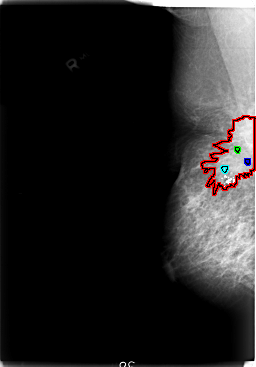

FILE: B_3025_1.RIGHT_CC.OVERLAY

TOTAL_ABNORMALITIES 4

ABNORMALITY 1

LESION_TYPE MASS SHAPE IRREGULAR-ARCHITECTURAL_DISTORTION MARGINS ILL_DEFINED-SPICULATED

ASSESSMENT 5

SUBTLETY 5

PATHOLOGY MALIGNANT

ABNORMALITY 2

TOTAL_OUTLINES 1

ABNORMALITY 3

LESION_TYPE CALCIFICATION TYPE PLEOMORPHIC-FINE_LINEAR_BRANCHING DISTRIBUTION SEGMENTAL

ABNORMALITY 4